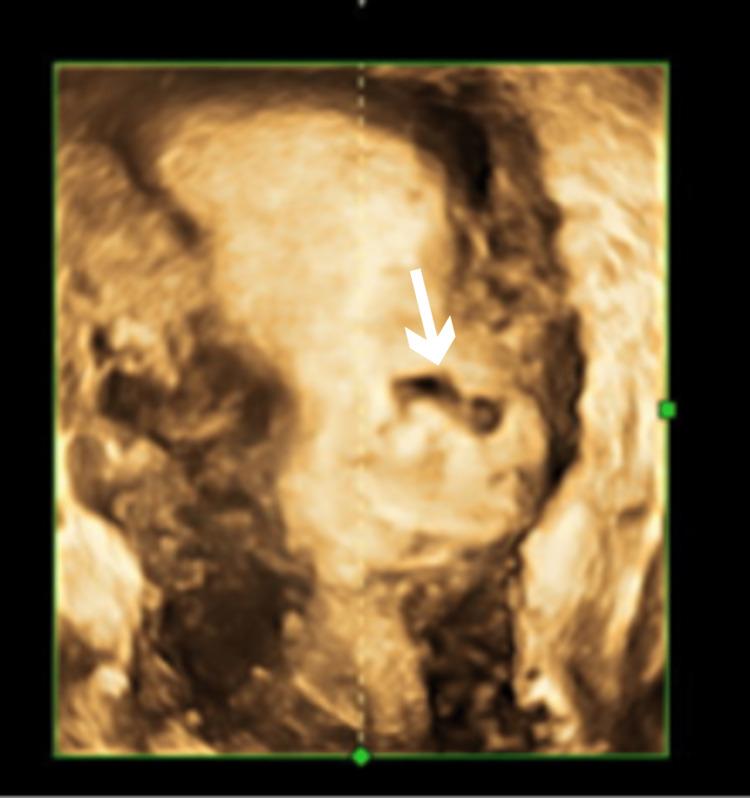

Ectopic pregnancy in the scar of a previous cesarean section contributes to significant maternal morbidity in the first trimester due to a significantly higher risk of uterine rupture if left undetected. The routine scans done in the first trimester serve as an important screening tool in the detection of such an ectopic pregnancy. Early detection can aid in making a paradigm shift from a surgical to a more conservative approach for the management of such pregnancies. Here, we report a case of a cesarean scar pregnancy diagnosed in the sixth week of gestation which was managed non-surgically with methotrexate and intracardiac potassium chloride injection.

既往剖宫产瘢痕处的异位妊娠,若未被发现,由于子宫破裂风险显著更高,会在孕早期导致严重的孕产妇发病。孕早期进行的常规扫描是检测此类异位妊娠的重要筛查工具。早期发现有助于将此类妊娠的管理模式从手术治疗转变为更保守的方法。在此,我们报告一例在妊娠六周时诊断出的剖宫产瘢痕妊娠,该病例通过甲氨蝶呤和心内注射氯化钾进行了非手术治疗。